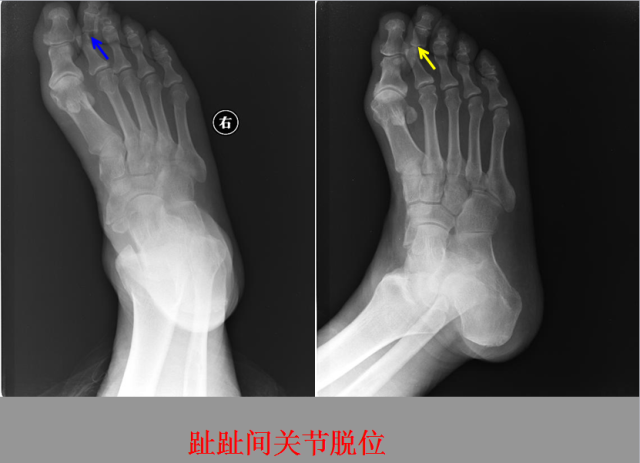

关节脱位篇

02

定义:关节脱位是暴力、关节感染、附近软组织挛缩或先天骨发育障碍造成的关节对位关系部分或完全脱离,即为半脱位或脱位。临床上以创伤性脱位*常见。